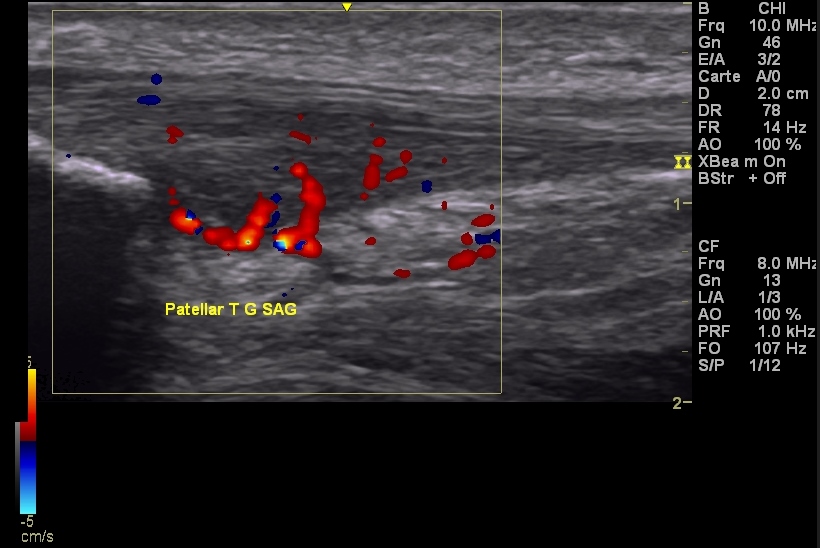

Les pathologies tendineuses (tendinopathies, bursite, calcifications, ruptures):

Mais aussi interventionnelle (injections écho-guidées d’acide hyaluronique, infiltration écho-guidée du mur méniscal, tendineuses ou musculaires):